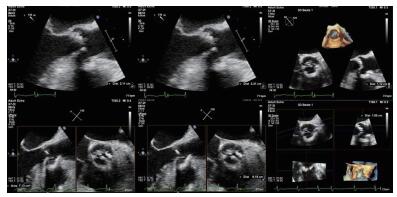

(1)经食道超声评估瓣环、窦、冠脉高度和升主动脉由于患者术前无法行CT检查,无法获知其主动脉根部情况,术中通过食道超声(2D和3D)评估主动脉根部结构。本病例术中经食道超声评估提示:主动脉瓣瓣环内径2.11 cm,主动脉窦部直径2.89 cm×2.84 cm×2.84 cm,右冠开口高度1.12 cm,左冠开口开口1.05 cm,升主动脉无明显增宽(图 3)。

|

| 图 3 患者术中经食道超声心动图 |